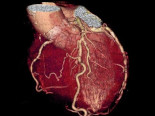

X線CT(コンピュータ断層)撮影装置(64マルチスライスCT)(1台)

X線を利用して人体の様々な断面の画像を得ることができます。

内臓脂肪量の計測も行っています。(健康管理センター オプション)